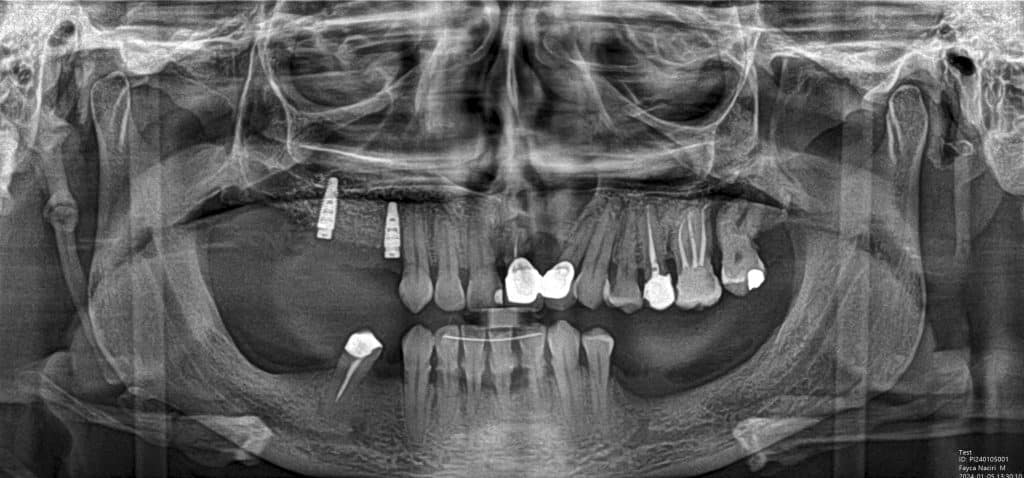

Case of the day where i extracted the 34-35-36 and an immediate placement of 2 implants in the 34-36 sites

sticky bone grafting GTO by osteobiol was used with straumann xenograft